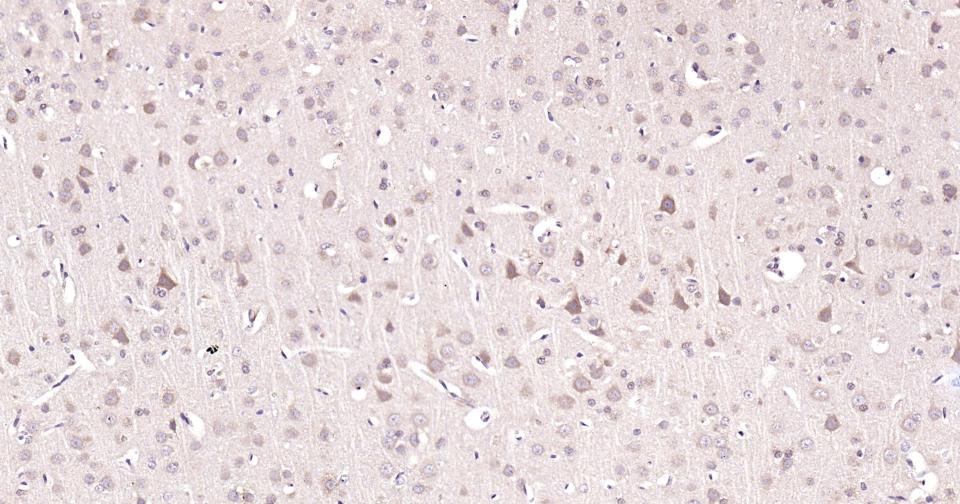

Paraformaldehyde-fixed, paraffin embedded Rat Cerebrum; Antigen retrieval by boiling in sodium citrate buffer (pH6.0) for 15 min; Antibody incubation with TPH Monoclonal Antibody, Unconjugated(bsm-61227R) at 1:200 overnight at 4°C, followed by conjugation to the SP Kit (Rabbit, SP-0023) and DAB (C-0010) staining.